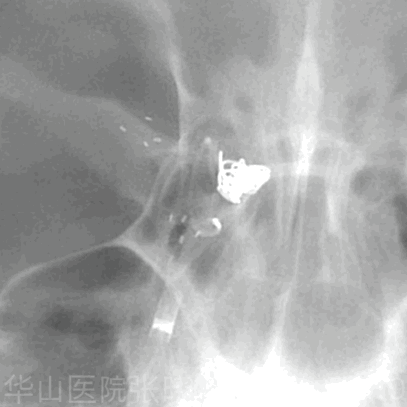

Figure 6 GIF. Target 360 ultra 4mm*6cm. Adjusting the framing to embolize the daughter sac with partial loops. 图 6. Target 360 ultra 4mm * 6cm弹簧圈。调整成篮,以部分圈栓塞子瘤。

Figure 7 GIF. Target 360 ultra 2mm*4cm. Partial loops embolized the daughter sac. 图 7. Target 360 ultra 2mm*4cm弹簧圈。部分圈栓塞子囊。

Figure 8 GIF. Target 360 ultra 2mm*4cm. 图 8. Target 360 ultra 2mm*4cm弹簧圈。